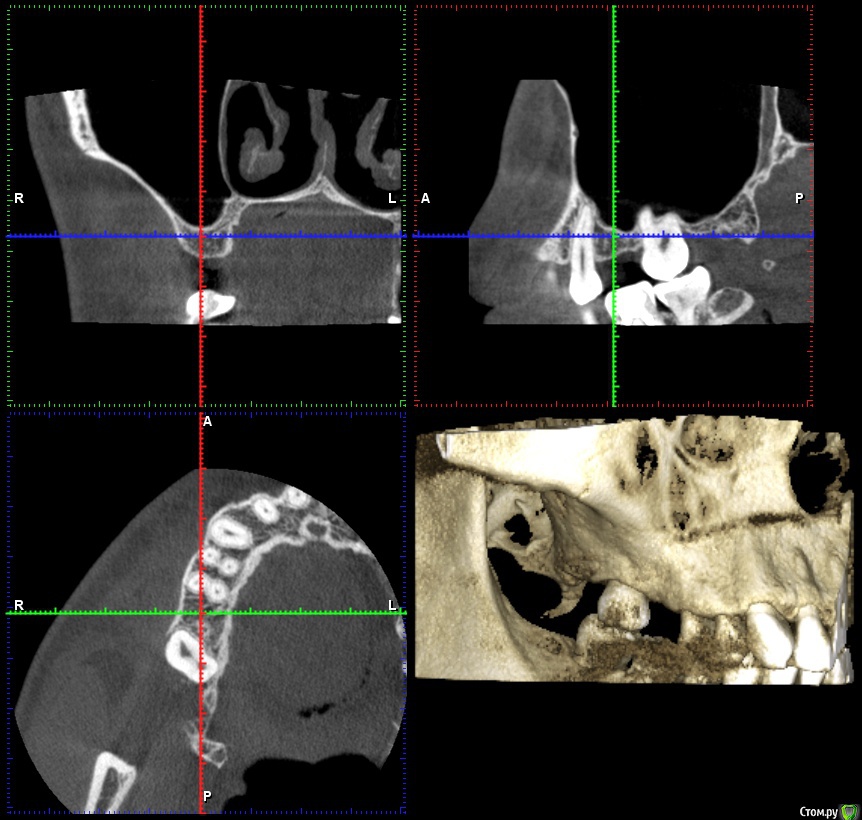

fallnighter Опубликовано 27 августа, 2020 Поделиться Опубликовано 27 августа, 2020 Здравствуйте, уважаемые врачи и иные пользователи форума! Очень прошу вас изучить мой случай и ответить на интересующие вопросы. 01.08.2020 была операция, установлен имплантат AnyRidge на место 6-го зуба сверху, плюс закрытый синус-лифтинг (было только 7 мм. кости), плюс сразу же установка формирователя десны. Неделя после была ужасной, т.к. очень сильно ныли соседний 5 и 4 зуб, сидел на обезболивающих, но в итоге всё благополучно стихло. Для спокойствия также делали прицельный снимок через несколько дней после операции, чтобы убедиться что с этими ноющими зубами всё в порядке (убедились).Прошел почти месяц, болей и дискомфорта нет, разве что волнует меня формирователь десны. Он как будто "вылез" частично, т.е. ранее десна была ниже, даже через неделю после операции, когда от отека уже не осталось и следа, а сейчас поднялась. Прикладываю КТ сегмента до операции и сразу же после. Прицельного снимка, к сожалению, нет (остался в электронном виде в клинике). Также прикладываю фото того, как сейчас выглядит формирователь. Подскажите, пожалуйста, нормально ли он сейчас стоит, есть ли повод для беспокойства? Забивается пища рядом с ним, стараюсь тщательно соблюдать гигиену и пользоваться ирригатором, но очень настораживает что он несколько "оголился" из десны, ведь раньше такого не было. Спасибо огромное всем, кто откликнется! https://yadi.sk/d/EYQJ8w0wxr7EXw Ссылка на комментарий